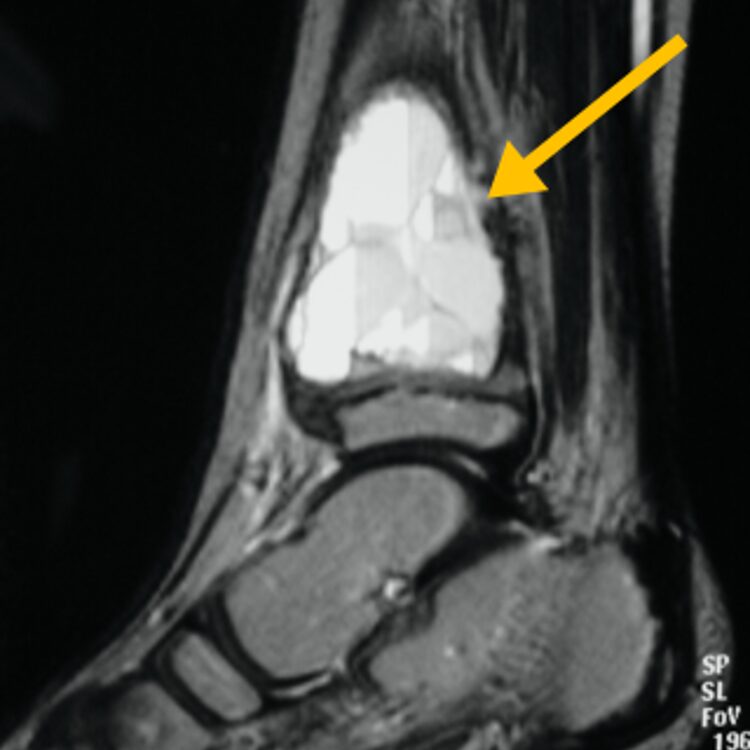

Radiographic imaging is used to help form a diagnosis of ABC. These include X-Ray, MRI, CT and Bone Scans.

An example of an ABC X-Ray (Figure 1A) and an MRI (Figure 1B) with fluid fluid levels are shown.